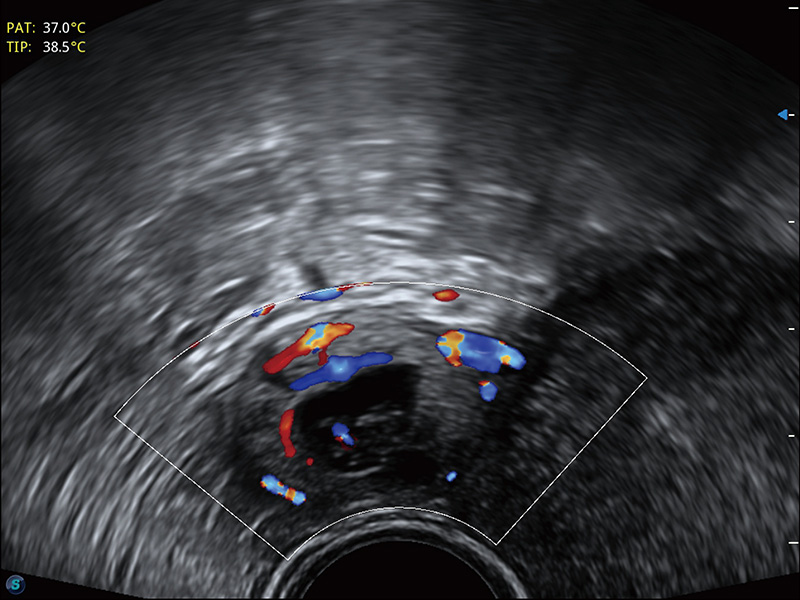

“生育问题”即关系民族复兴,也关系亿万家庭的幸福。随着婚育年龄推迟、社会压力增加等因素,越来越多人群也面临着“生不出、生不好”的问题。辅助生殖作为治疗不孕不育最有效的方法之一,也逐渐成为育儿新希望。而超声检查能为生殖需求人群的初诊评估提供宝贵的信息。 P20 Elite是百老汇电子游戏官网匠心打造的一款生殖应用型彩超。她继承百老汇电子游戏官网高端极光平台,突破性地将多款新型芯片及硬件模块进行整合,均衡了高端系统性能与小巧灵动机身。P20 Elite卓越的图像质量搭载专科探头,旨在为您提供全面的辅助生殖解决方案。

P20 Elite配备了丰富的生殖探头群和临床应用功能,在卵泡监测、穿刺取卵、胚胎移植、妊娠确认等领域,为生殖需求人群提供了新的临床机会,重新定义高端超声如何应用于生殖健康检查。